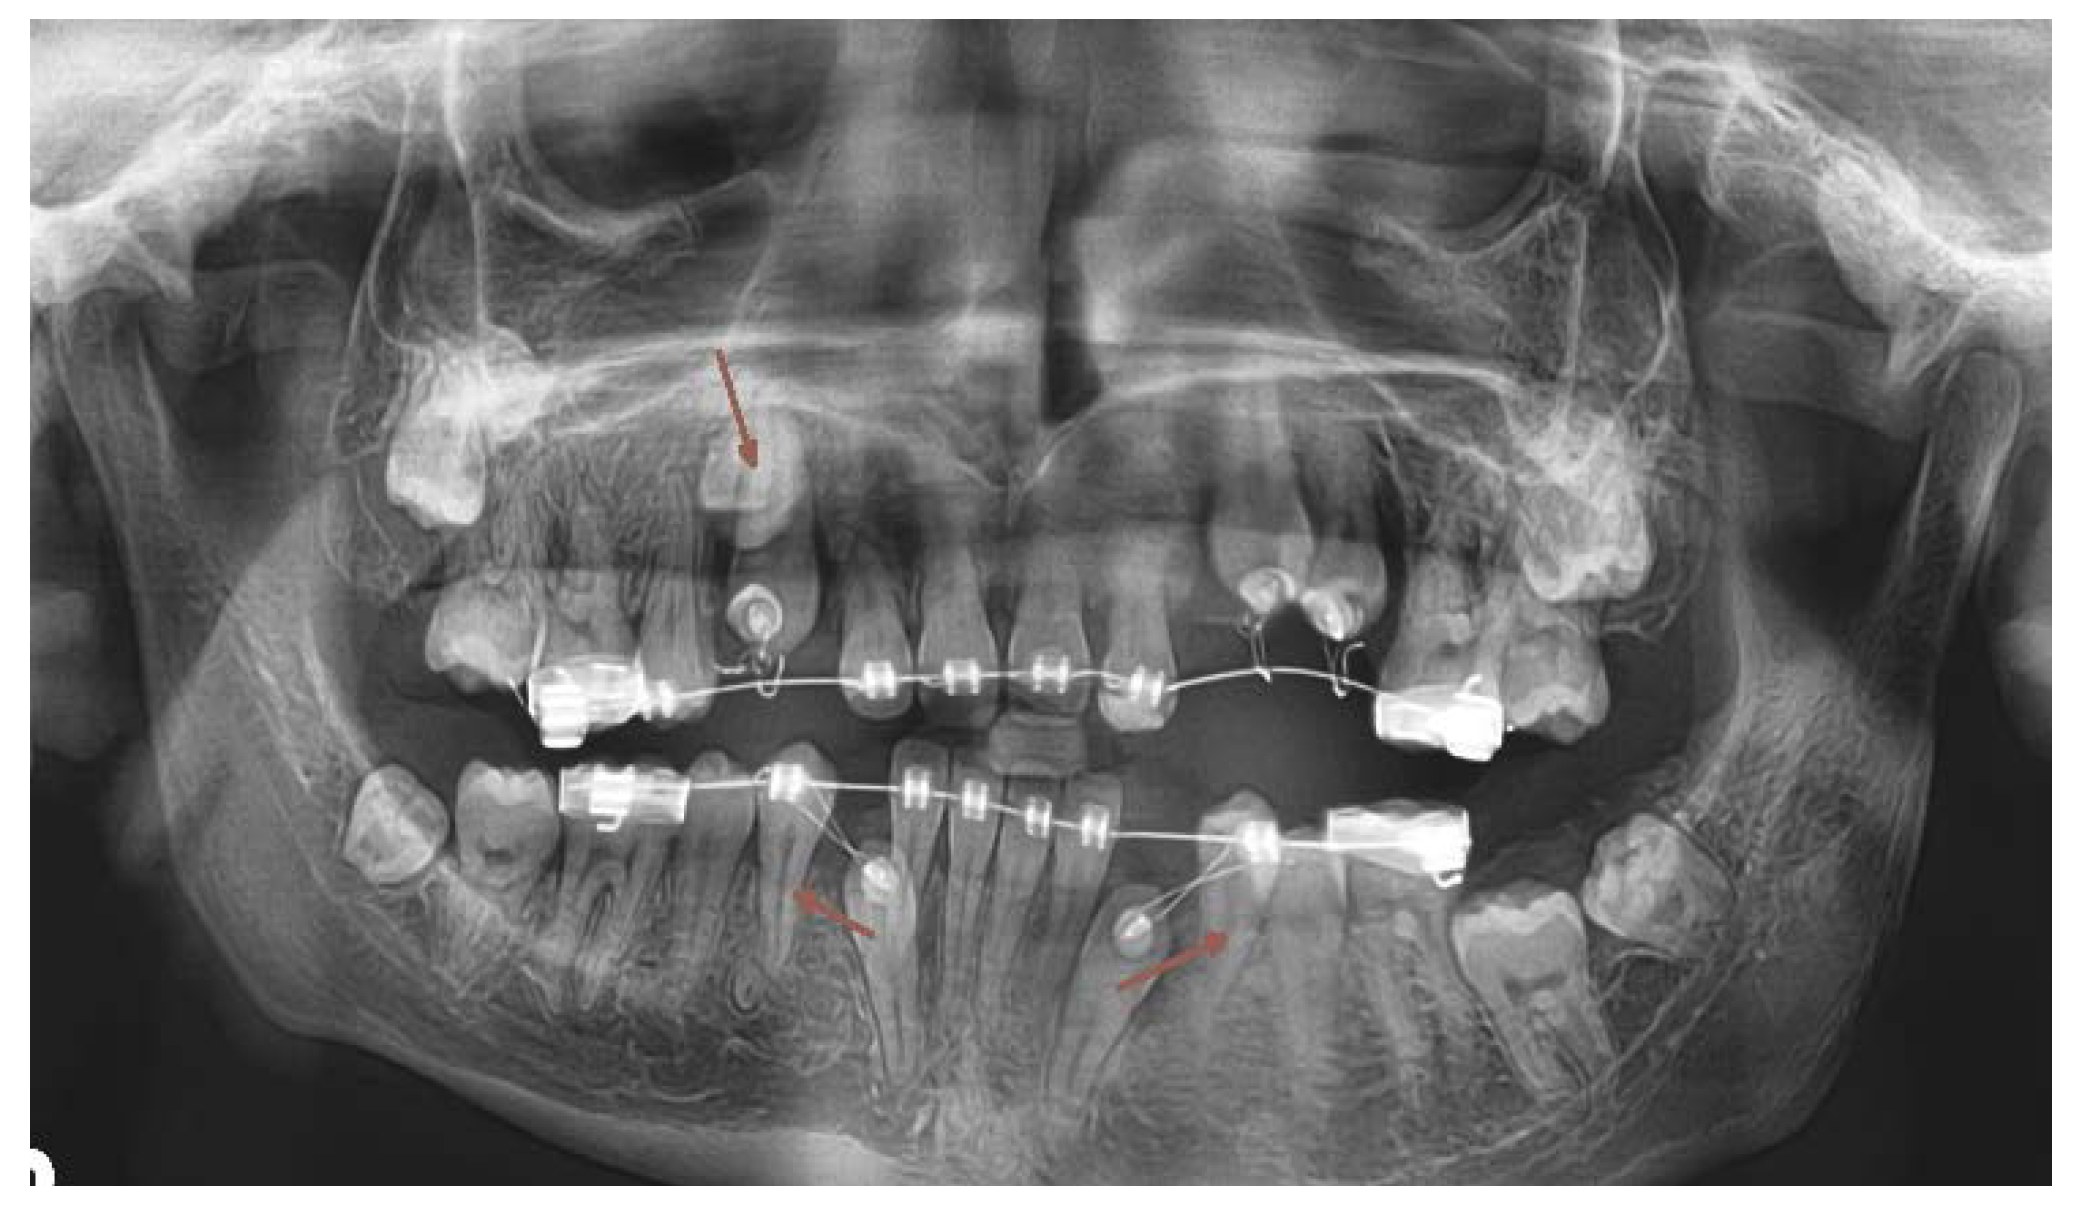

In April 2018, the patient´s age was 13 years 5 months, the dental age was 8 years. Under general anesthesia, two supernumerary teeth in the lower right and one in the lower left quadrant were extracted. (Figure 5.,10.) 3 primary teeth were extracted as well (73,83 and 84). This cleared the way for the anticipated spontaneous eruption of lower canines and first premolars. (Figure 10.) One supernumerary tooth with an underdeveloped root in the area of 35 was subsequently extracted from the chair under local anesthesia. (Figure 10.) Unfortunately the path of eruption of the 33 and 43 was too close to the apical area of the 42 and 32, (Figure 10, 11.), so an additional surgical intervention was planned, in local anesthesia, to expose the lower canines and redirect their eruption. This required already a fixed orthodontic appliance placement to anchor proposed lower canine traction.

Figure 10. OPG x-ray after the 2nd surgical intervention under general anesthesia. (2018).